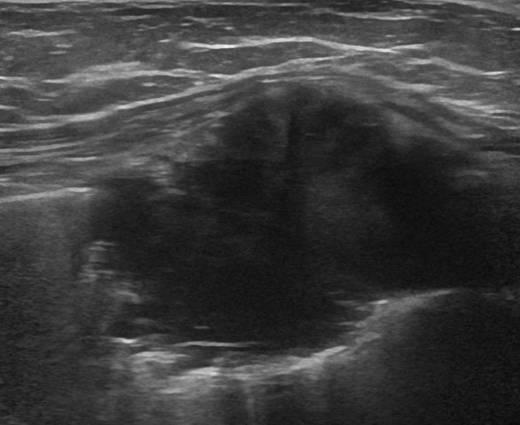

Di căn thành ngực

» Thông tin: Nam giới – 64 tuổi.

» Lâm sàng: Khối thành ngực / K vòm.